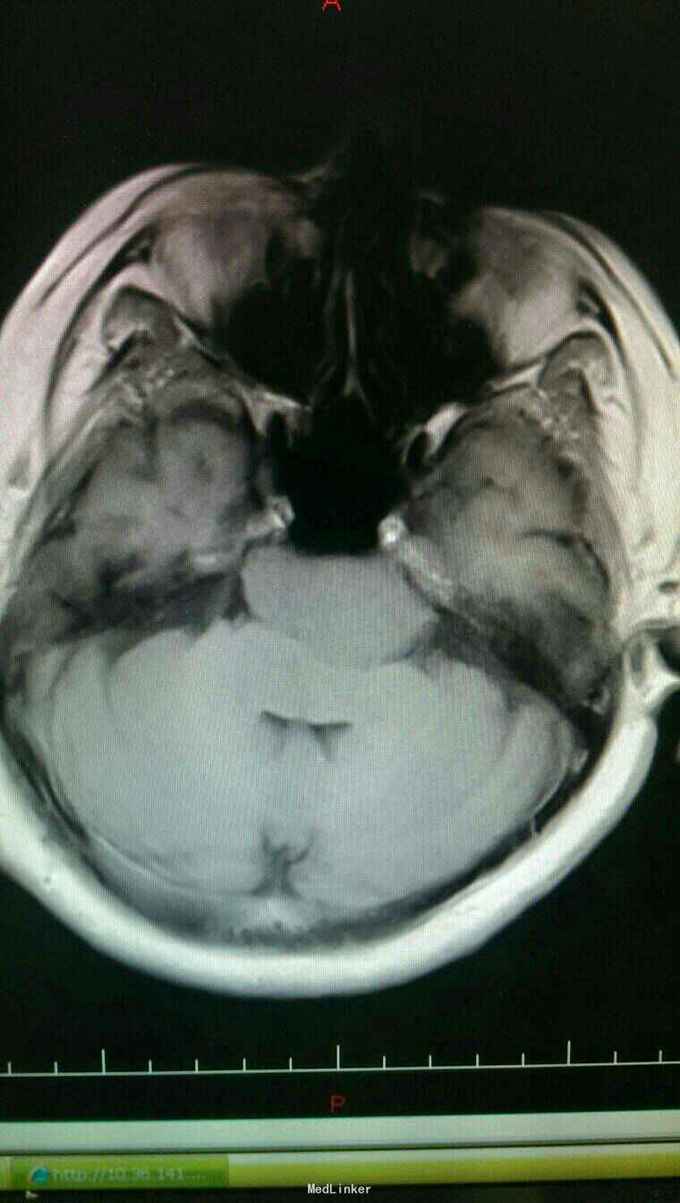

患者以头晕伴走路不稳一个月为主诉入院。患者于入院一个月前自觉头晕,无头痛,无恶心,呕吐。走路不稳,无四肢抽搐及二便失禁。

查体:神志清楚,语言流利。双侧瞳孔等大正圆,直径3.0毫米,光反射灵敏。饮水呛咳,无声音嘶哑。颈软,四肢肌力正常,生理反射存在,病理反射未引出。

入院诊断:岩斜区脑膜瘤。完善术前准备,于全麻下行右侧颞下入路,岩斜区肿瘤切除,术中保留拉贝静脉,剪开小脑幕,近全切除肿瘤。

患者术后病情稳定,岩斜区位于颞骨岩部背面与枕骨斜坡部的岩斜裂汇合处,从岩骨尖至颈静脉孔。内侧至斜坡中线,外侧至第Ⅴ、Ⅶ和Ⅷ脑神经,上缘为鞍背,下缘为颈静脉孔水平;下方为枕骨大孔区。岩斜区脑膜瘤由于位置深,毗邻重要解剖结构,很难实现肿瘤全切除,且有较高的术后致残率,一直是神经外科手术的治疗难点。颅内脑膜瘤约0.3%~1.0%起源于岩斜区,是岩斜区最常见病变。它向上可侵犯岩骨尖、小脑幕、Meckel腔、鞍旁和海绵窦;向下侵犯内听道和颈静脉孔;向内侧达脑干和椎-基底动脉。当肿瘤很大时,可包绕同侧Ⅲ~Ⅺ脑神经。患者临床可表现头痛、复杂的脑神经麻痹、共济失调等症状,严重者表现为偏瘫、认知功能障碍。岩斜区脑膜瘤多数表现良性过程,目前,仍以手术切除为首选治疗方式。 岩斜区脑膜瘤手术技术非常关键,需要熟悉岩斜区解剖关系并有丰富的显微操作经验。在术前放置腰穿引流,或术中甘露醇应用可明显降低脑组织压力,减少牵拉造成的副损伤。提前对脑膜瘤基底的处理可有效避免肿瘤持续出血造成的蛛网膜界面消失。肿瘤的生长将神经、血管拉伸或包绕,尤其是复发的肿瘤,会破坏蛛网膜界面,侵犯脑干软脑膜。手术时应仔细分辨和保护。肿瘤囊壁与神经、血管外膜和脑干粘连,不应勉强分离,以保护下方结构。 待术后平稳复查头Ct。